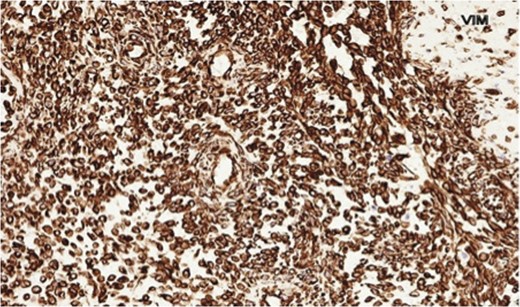

The histopathology demonstrated that the breast was partially replaced by a partly cystic and partly solid necrotic lesion. The cystic cavity contained blood clots. A microscopic examination showed an atypical undifferentiated spindle cell lesion with a fascicular architecture, pleomorphism and marked mitotic activity with areas of ulceration and necrosis (Figs 1 and 2). The initial set of immunostains performed showed that tumour cells were negative for cytokeratins (Fig. 3), S100 and LCA. The tumour cells showed diffuse and strong vimentin positivity (Fig. 4). Further immunocytochemical labelling showed weak expression of CD99, patchy strong expression of CD10 and patchy weak expression of smooth muscle actin. Cytokeratins (CAM 5.2) and EMA were expressed and there was no tumour-specific expression of CD34, desmin or myogenin. Fluorescent In-situ hybridization analysis failed to demonstrate evidence of a t(x:18) translocation using the LYS-SYT break apart probe. The diagnosis of a Grade 3 undifferentiated spindle cell sarcoma was made and although the tumour was reported to have a clear resection margin (5 mm) in most areas, the presence of necrosis and granulation tissue reaching the deep margin made the status of the margin uncertain.

Photomicrograph showing negative cytokeratin AE1/AE3 staining in spindle cells.